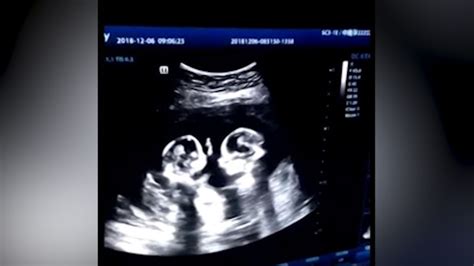

Ako sa zisťuje typ dvojčiat?

Typ dvojčiat sa zvyčajne dozvie nastávajúca matka už počas tehotenstva prostredníctvom ultrazvukového vyšetrenia. Počet placenty a plodových vakov je kľúčovým ukazovateľom. Spoločná placenta alebo plodový obal jasne naznačuje jednovaječné dvojičky. Ak sa na ultrazvuku javia dvojičky ako bichoriálne a biamniálne, lekár s istotou nepotvrdí, či ide o jednovaječné alebo dvojvaječné dvojičky. V prípade umelého oplodnenia, kedy sa do maternice vložilo viac oplodnených vajíčok, sa automaticky predpokladá, že ide o dvojvaječné dvojičky, ak sa uchytilo viacero embryí.